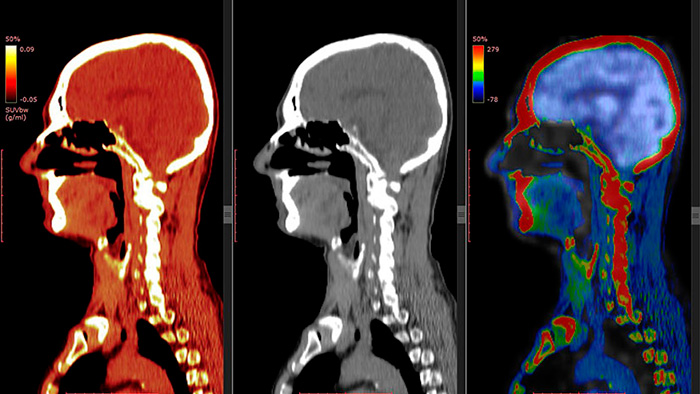

LOS COLORES DE LA GLUCOSA La Tomografía por Emisión de Positrones (PET, por su sigla en inglés) es una técnica de diagnóstico no invasiva que permite realizar imágenes que muestran el metabolismo y el funcionamiento de tejidos y órganos, basándose en el consumo de glucosa. La información obtenida es analizada computacionalmente y se construye una representación de los diferentes niveles de funcionamiento con escala de colores: rojo, naranjo y amarillo significan un aumento de la actividad metabólica; en tanto el verde o el azul indican una disminución de la misma. Es importante recordar que esta es una abstracción construida a través de algoritmos matemáticos y no una imagen real. Además, un diagnóstico por esta vía no está validado empíricamente en el caso de los trastornos mentales. (Imagen: Shutterstock)

En el caso de las neuroimágenes funcionales, se han ocupado diversas técnicas, las más importantes ligadas a la medicina nuclear. Entre ellas el SPECT (single photon emission computed tomography) y el PET (positron emission tomography). Se trata de técnicas no invasivas que miden la distribución  de glucosa, marcada con un radiofármaco de duración ultracorta, en diferentes tejidos, como el cerebro. El conocimiento de dicha distribución permite saber si existe actividad aumentada o disminuida. La información obtenida es analizada computacionalmente y se construye una imagen que representa los diferentes niveles de funcionamiento con escala de colores: rojo, naranjo y amarillo significan un aumento de la actividad metabólica; en tanto, verde y azul indican una disminución de la misma.

Con la comparación de los patrones conocidos de la actividad metabólica normal se puede llegar a saber cuáles son las áreas alteradas. Aunque estas coloridas imágenes son espectaculares, es importante recordar que se trata de una representación construida a través de algoritmos matemáticos y no una imagen real. Aunque estas son de utilidad en la investigación, aún son de limitado uso en el ámbito clínico. Esto porque los trastornos mentales son heterogéneos en los patrones funcionales cerebrales asociados, de manera que un diagnóstico por esta vía no está validado empíricamente. Su uso se restringe a discriminar distintos tipos de demencia y   a evaluar el daño ocasionado por el consumo de sustancias, como la cocaína.